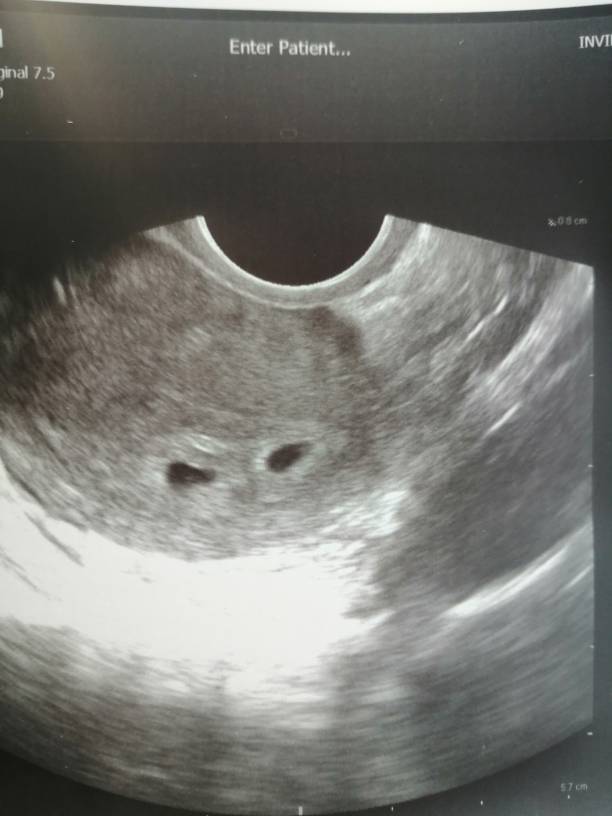

Kształty chyba na tym etapie nie decydują o niczym[emoji6] ciesz się[emoji3]Dziewczyny byłam dziś na usg. Lekarz mówi że jest dobrze, są dwa pęcherzyki ale mnie martwi ich nierówny krztalt. Zobacz załącznik 1085860